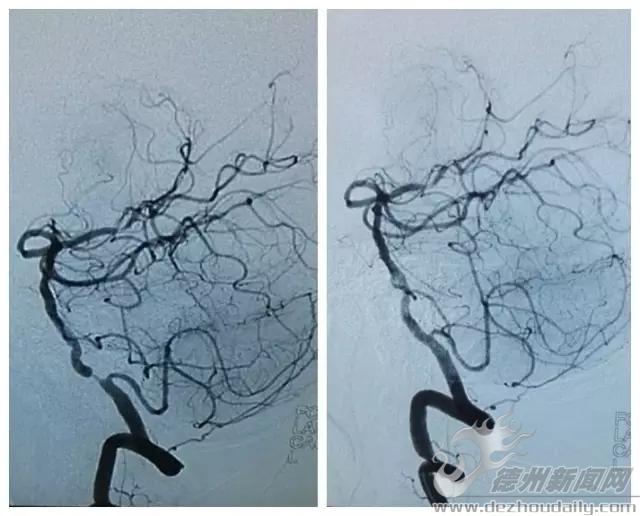

心,脑血管支架一次搞定!德州首例!|德州云-德州晚报全媒体

德州联合医院成功实施首例脑血管介入支架成形术